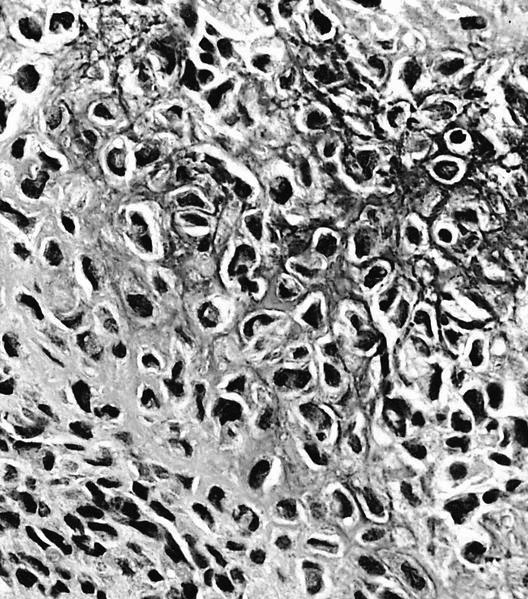

Microscopic (histologic) description

- Composed of round or polyhedral chondroblasts with abundant eosinophilic cytoplasm and well defined cell borders; spindle shaped cells may be focal (Ann Diagn Pathol 2003;7:205, Cancer 1972;30:401)

- Nuclei are oval, hyperlobulated with grooves

- Pericellular lace-like or chicken wire type calcification among degenerative chondroblasts

- Chondroid matrix almost always present (pink rather than blue matrix)

- May have marked cellularity, intracytoplasmic glycogen granules, mitotic figures, necrosis and osteoclast type giant cells

- Aneurysmal bone cyst-like change is common (Skeletal Radiol 2010;39:583)

Microscopic (histologic) images

- Aneurysmal bone cyst:

- Primary: multiloculated, blood filled, destructive, cystic lesion; USP6 gene rearrangements

- Secondary: can be associated with chondroblastoma, giant cell tumor, osteoblastoma and osteosarcoma (Clin Imaging 2020;62:23)

A. Chondroblastoma. Chondroblastomas commonly present in the second decade of life as a singular, well defined lucent lesion within skeletally immature long bones. Characteristic histopathological features include sheets of chondroblasts admixed with osteoclast-like giant cells in a chondroid matrix and focal chicken wire type calcification. Chondroid fibromas typically lack chicken wire type calcification. Chondroblastoma-like osteosarcomas generally display an infiltrative growth pattern with marked cytologic atypia. Chondroid matrix is not commonly seen in giant cell tumor of bone.